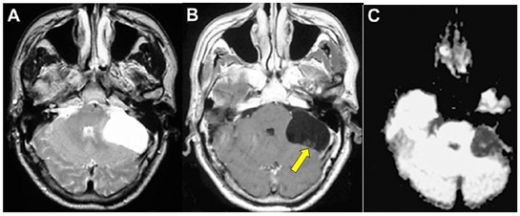

Beyinde kitle ameliyatı, genellikle tümörler, kist veya diğer anormal oluşumların cerrahi olarak çıkarılması amacıyla yapılan bir işlemdir. Bu tür bir ameliyat, beyin dokusuna doğrudan müdahale gerektiği için belirli riskler taşır ve sonrasında hastalar için çeşitli zorluklar ortaya çıkabilir. İşte bu makalede, beyin kitle ameliyatının riskleri ve sonrası hakkında detaylı bir inceleme yapılacaktır. 1. Beyin Kitle Ameliyatının Riskleri Beyin kitle ameliyatı, birçok risk barındırır. Bu riskler arasında şunlar bulunmaktadır: